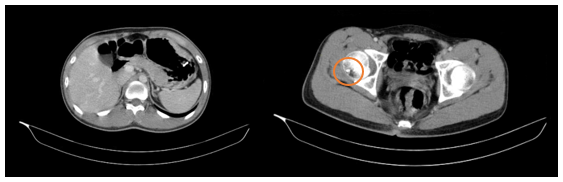

- Nội soi dạ dày: Thân phình vị, thân vị có đám niêm mạc co kéo, hội tụ, lõm ở trung tâm kích thước~ 3.0cm, bề mặt niêm mạc biến đổi

Hình 2

. Hình ảnh các polyp ở dạ dày (mũi tên đỏ). Niêm mạc dạ dày co kéo, lõm ở trung tâm (mũi tên xanh)

- Nội soi đại tràng: Phần quan sát được: Dọc đại tràng có nhiều polyp, tập trung ở đại tràng sigma kích thước ~ 0.3 - 0.6 cm. Trực tràng có nhiều polyp kích thước ~ 03-0.6 cm.

Hình 3

. Hình ảnh các polyp rải rác ở đại tràng (mũi tên đỏ)